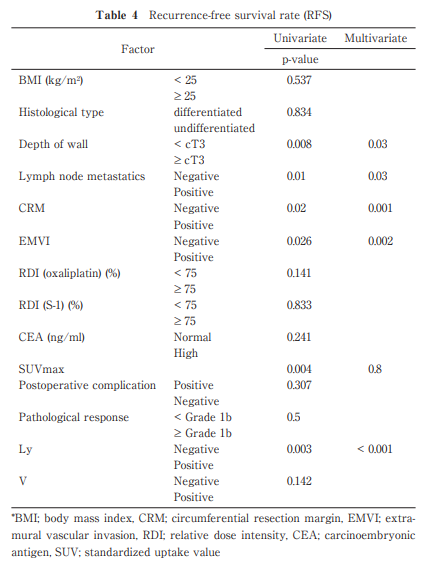

The Usefulness of Neoadjuvant Chemotherapy (S-1/Oxaliplatin) for Locally Advanced Mid-low Rectal Cancer

https://doi.org/10.51040/dkmj.2024-007

Keisuke Ihara et al.

Published online : December 27 , 2024